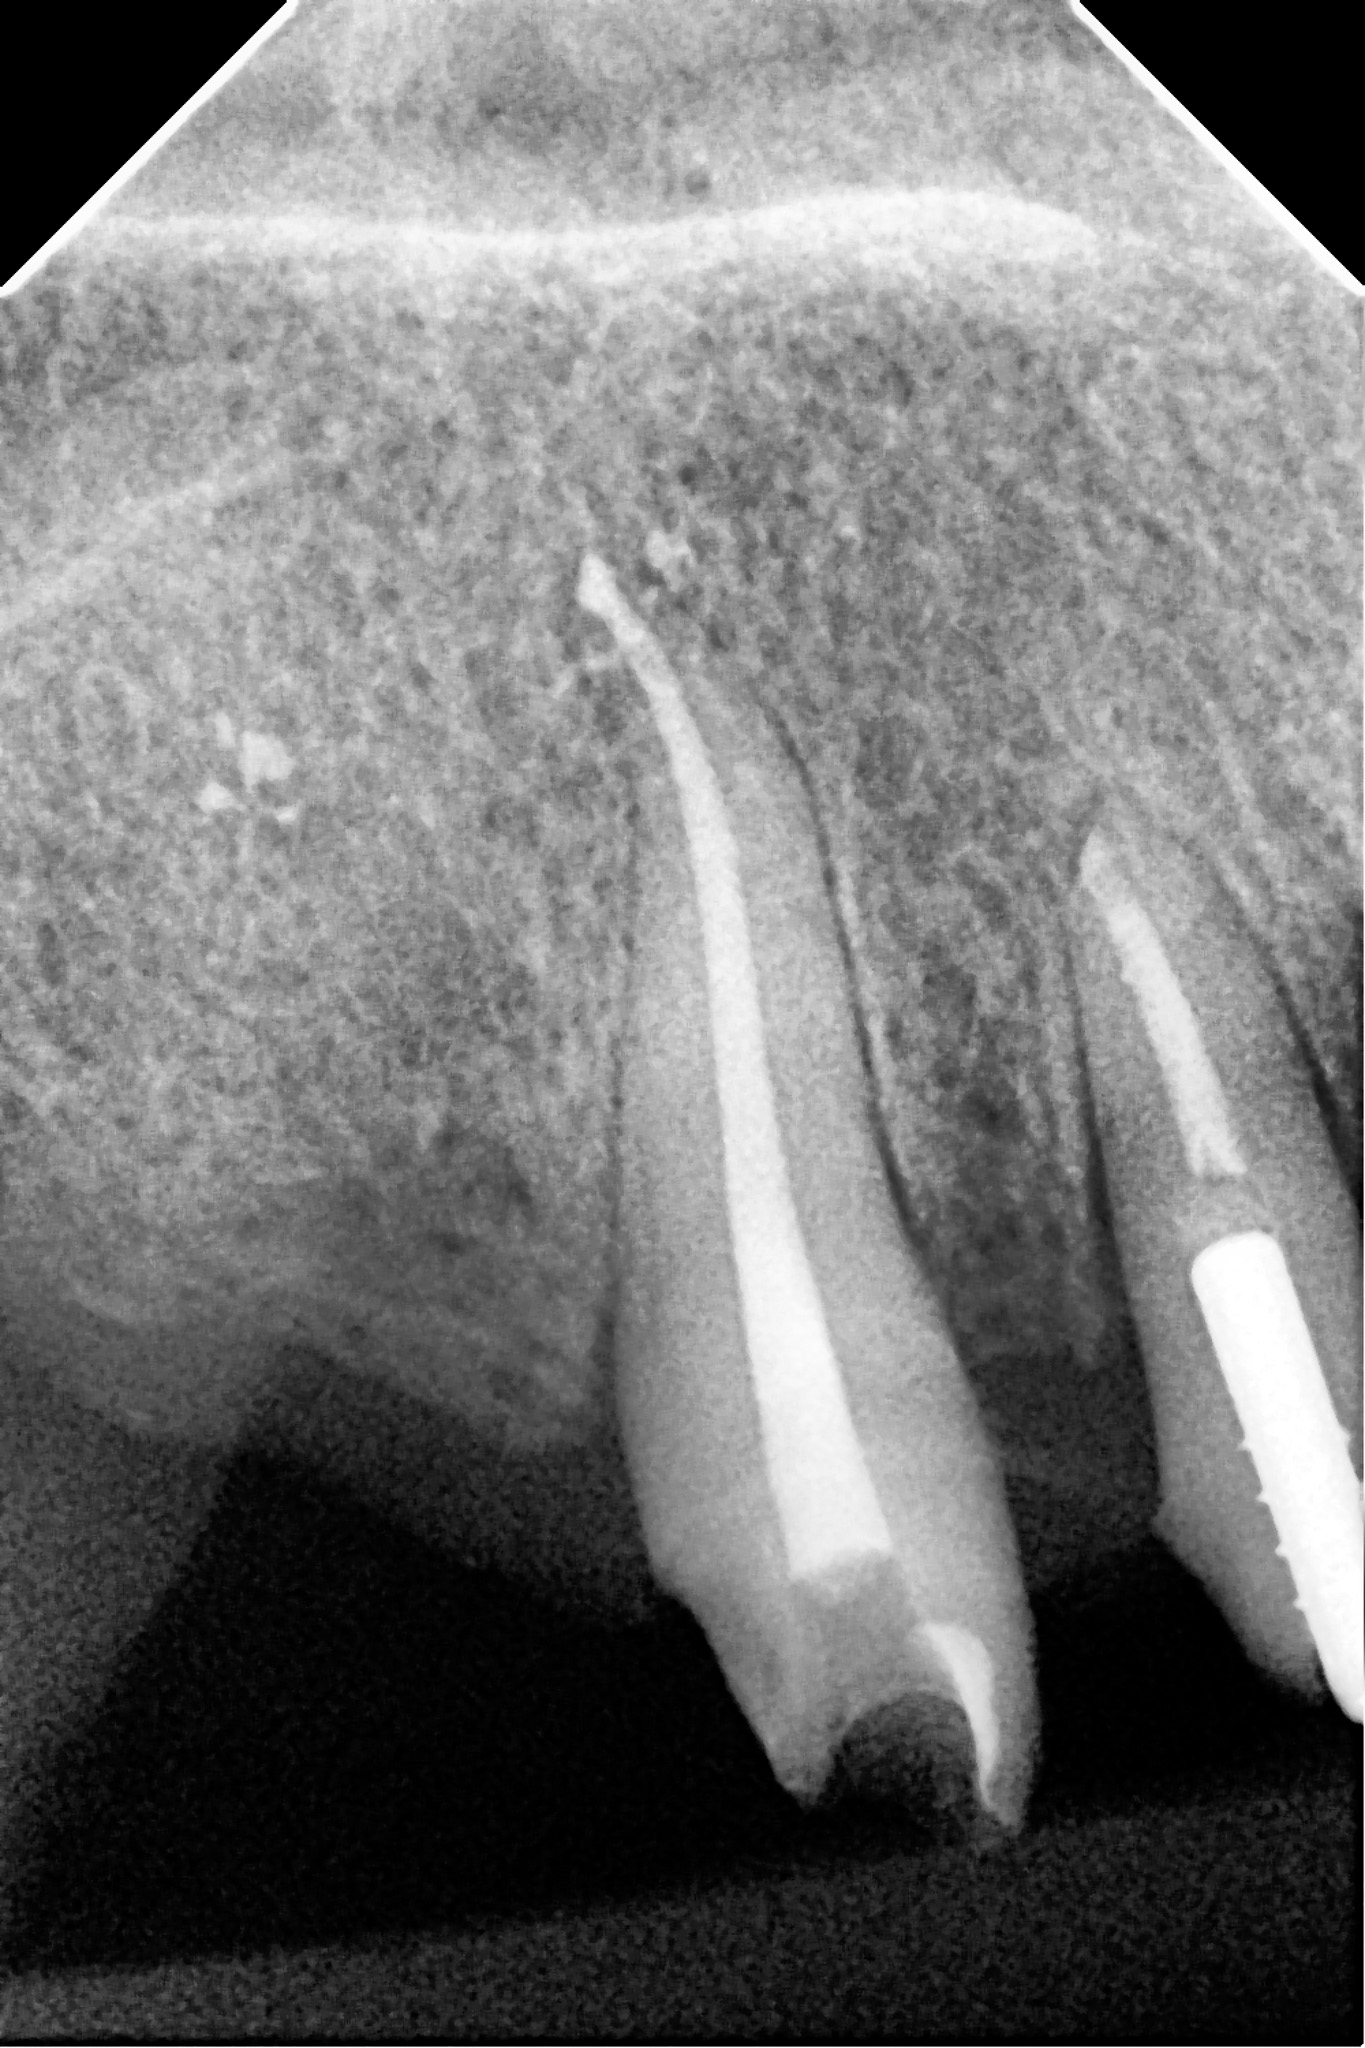

Pacjent zgłosił się do gabinetu w celu zaopatrzenia złamanego zęba (kła) w koronę protetyczną. W badaniu radiologicznym widoczna jest resorpcja materiału wypełniającego kanał po dawnym leczeniu endodontycznym oraz tworząca się zmiana zapalna w okolicy wierzchołka korzenia; z uwagi na konieczność wykorzystania zęba jako filar protetyczny przeprowadzono powtórne leczenie kanałowe (ReEndo) z wykorzystaniem nowoczesnych narzędzi rotacyjnych oraz mikroskopu zabiegowego. Kanał wypełniono szczelnie techniką obturacji płynną falą gutaperki (wypełnienie na ciepło).

Ząb posłużył do stabilnej odbudowy protetycznej.